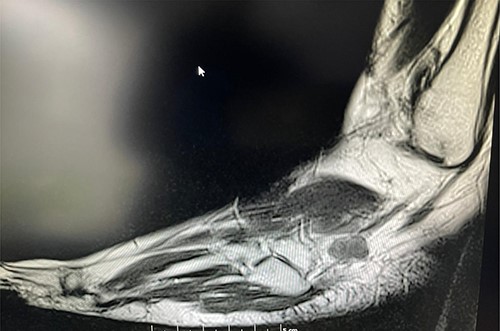

A 50-year-old lady presented to us with a lump in her left foot on the lateral aspect at the level of the calcaneocuboid joint for a 1-year duration, which was associated with pain. She consulted her GP who advised an US scan. This revealed a lump over the dorsum of the left foot on the lateral side. She also had a magnetic resonance imaging (MRI) scan which was indeterminate (Figs 3 and 4). It was reported as a suspected sarcoma. She was then referred to the Sheffield sarcoma unit where she underwent a biopsy of the swelling; which was reported as angiomyolipoma (a benign swelling). She was not keen on excision initially, but as the swelling increased in size and started becoming painful, she underwent an excision of the lesion under our care and the histopathologic examination of the excised sample confirmed it to be angioleiomyoma. The post-operative period was uneventful and she was discharged from our care after 10 weeks. At this time, she was symptom-free and had a pain score of 0/10.

T1 MRI image of the soft tissue lesion over the lateral foot in Patient 2, which shows a lesion isointense to hypointense to the muscle.

T2 axial MRI image of the soft tissue lesion over the lateral foot in Patient 2 showing a lesion which is heterogeneous and slightly hyperintense to the muscle.

Similarly, in Case 2, the patient had an MRI scan which reported an indeterminate swelling suggestive of a possible sarcoma. As the MRI findings were not characteristic of the MRI findings of an angioleiomyoma, such as T1: isointense or hyperintense to muscle, T2: heterogeneous and slightly hyperintense to muscle and T1 C+ (Gd): homogenous to heterogeneous enhancement, suspicion of the sarcoma was reported from the MRI scan findings and referral to sarcoma unit was advised. This clearly shows that the US and the MRI scan findings can suggest a different diagnosis, and a confirmed diagnosis was only established following excision and histopathological examination of the excised lesion. Usually, angioleiomyomas have a peripheral low-intensity signal rim corresponding to a fibrous pseudo capsule with adjacent vascular structures with isointense or hypointense to muscle on T1 images and heterogeneous and slightly hyperintense to muscle on T2 images.